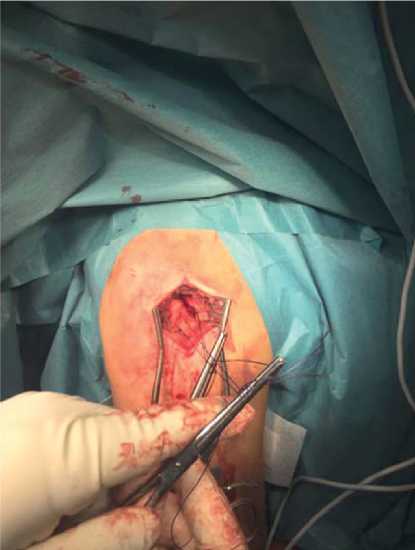

Применяли миниинвазивный доступ длиной 4–6 см на 1 см кпереди от акромиального отростка (рис. 2), послойно рассекали кожу, подкожную клетчатку, дельтовидную мышцу вдоль волокон; прошивание вращательной манжеты ротаторов осуществляли с дальнейшем рассечением ее по интервалу ротаторов и фиксацией на «держалки» (рис. 3), что обеспечивало доступ к суставной поверхности головки плечевой кости (точке введения штифта) [7]. Данную методику выполняли при переломах типа С и застарелых переломах типа В по АО.

Рис. 2. Разметка хирургического доступа

Рис. 3. Хирургический доступ. Кожа и подкожная жировая клетчатка рассечены. Сухожилия манжеты ротаторов прошиты и взяты на «держалки»